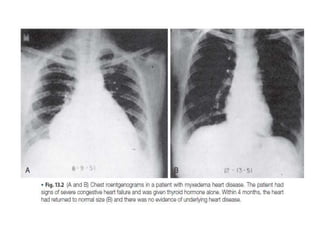

 Reduced myocardial contractility ,pulse rate, stroke volume and

bradycardia.

 Increased peripheral resistance leads to hypertension, particularly diastolic

HTN.

 Pericardial effusions seen in up to 30% of patients.

 Chest x rays findings are cardiomegaly , interstitial edema, myofibrillary

swelling, LV dilatation and pericardial effusion.